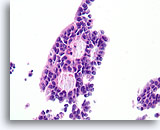

Papilloom, Borst FNA, Celblok.

Deze afbeelding van dezelfde FNA als in afbeelding 18 bevat een duidelijk papillaire architectuur.

10X

Papilloom, Borst FNA, Celblok.

Deze afbeelding van dezelfde FNA als in afbeelding 18 bevat een duidelijk papillaire architectuur.

10X

Papilloom, Borst FNA, Celblok.

Met een sterkere vergroting kan een gemengde celpopulatie gezien worden die het oppervlak en de onderliggende melkgangen bekleden. Een rij myoepitheliale cellen is zichtbaar tussen de ductale cellen en het onderliggende stroma (pijl). Let op de spleetachtige ruimte die kenmerkend is voor typische hyperplasie (open pijl).

40X

Papilloom, Borst FNA, Celblok.

Met een sterkere vergroting kan een gemengde celpopulatie gezien worden die het oppervlak en de onderliggende melkgangen bekleden. Een rij myoepitheliale cellen is zichtbaar tussen de ductale cellen en het onderliggende stroma (pijl). Let op de spleetachtige ruimte die kenmerkend is voor typische hyperplasie (open pijl).

40X